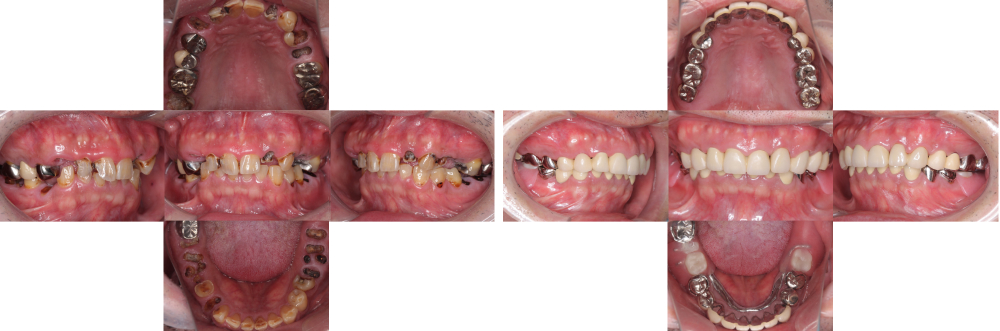

全顎保険治療

術前

術後

| 治療内容 | 全顎的に保険内で治療を行った |

|---|---|

| 治療期間・回数 | 約2.5年・約50回 |

| 費用 | 保険適用となります |

| リスク・副作用 |

|